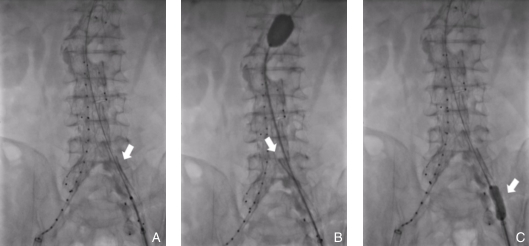

图4 注入纤维蛋白粘合剂过程 A:预置导管注入造影剂示踪;B:注入纤维蛋白粘合剂;C:纤维蛋白粘合剂在瘤腔内弥散;D:副肾动脉显影;E:调整导管位置;F:继续注入纤维蛋白粘合剂;G:腰动脉显影;H:调整导管位置角度,继续注射,腰动脉未显影Fig.4 Process of fibrin sealant injection A: Contrast injection through the pre-positioned catheter for tracking; B: Injection of fibrin sealant; C: Dispersion of fibrin sealant within the aneurysm sac; D: Visualization of an accessory renal artery; E: Adjustment of catheter position; F: Continued injection of fibrin sealant; G: Visualization of a lumbar artery; H: Adjustment of catheter angulation followed by continued injection, with no further visualization of the lumbar artery